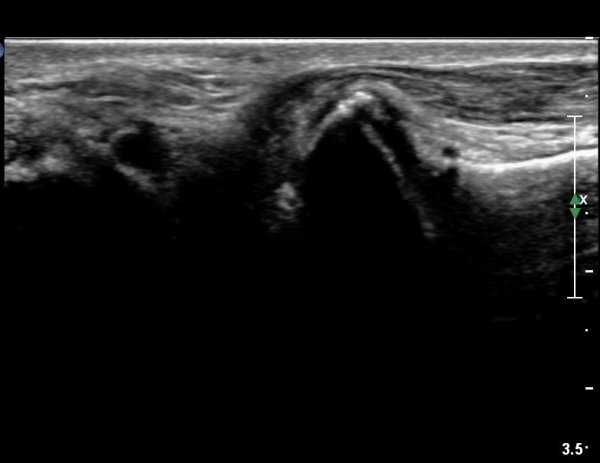

¹ß¸ñ °üÀý Á¾´Ü¸é°Ë»ç¿¡¼­ °æ¹ÌÇÑ °üÀý³» ºÎÁ¾À» º¸ÀÓ(»çÁø 1).

Àü°ÅºñÀδë Á¾´Ü¸é°Ë»ç¿¡¼­ Àü°Åºñ ÀδëÀÇ Àú¿¡ÄÚ ºÎÁ¶À» º¸ÀÓ(»çÁø 2).